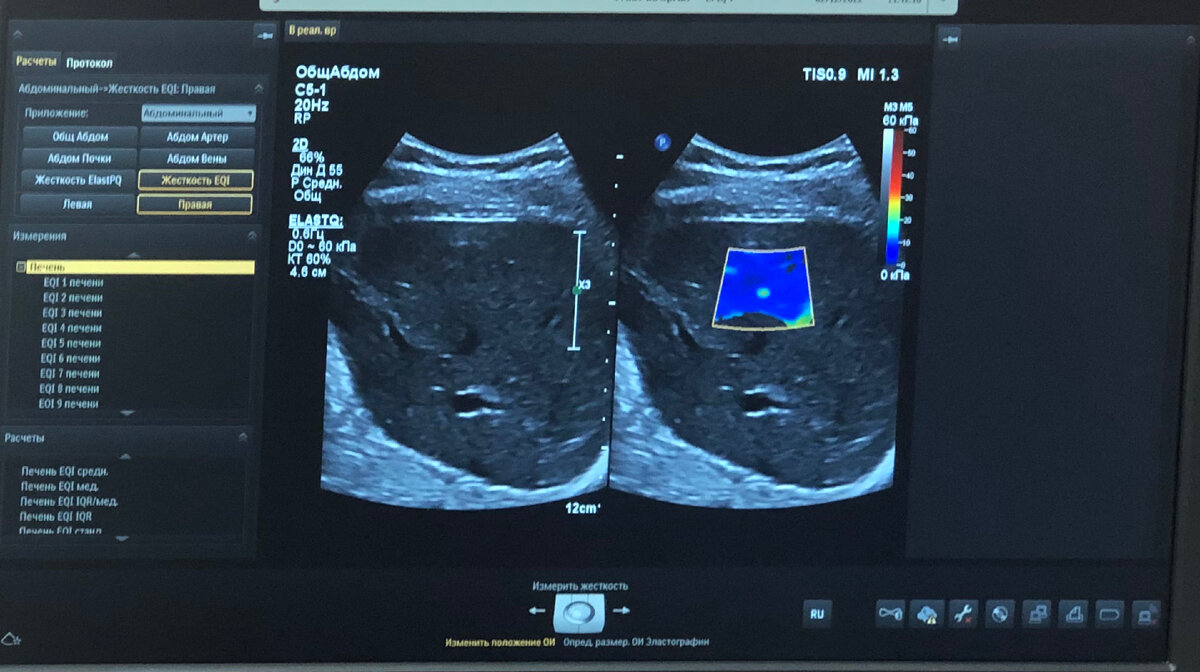

Я сейчас прохожу стажировку в клинике, где делают эластографию печени. Это, если по-простому, исследование жёсткости печени, насколько она эластична, насколько выражен фиброз, или того более, может быть уже цирроз. Пациенты приходят разные, но большая масса именно «циррозники». Многие товарищи-любители, кто еще имеет возможность, проверяют, как там у печени дела, терпит ли ещё.

Эластография печени